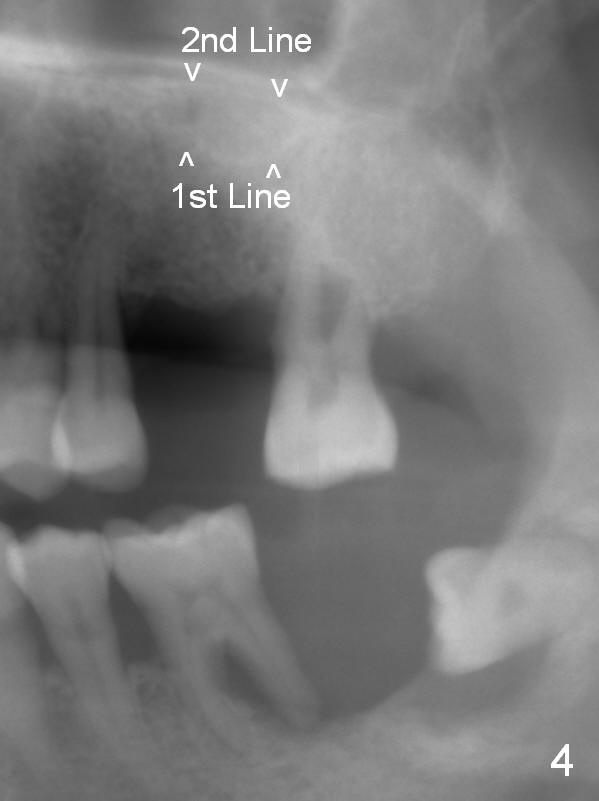

Implant placement at #31 reveals that bone width (bucco-lingual) is not a problem for a 64-year-old man. He requests implant placement at #7 and 14 (Fig.1,3), because the upper flipper has been lost. He wants to make sure that the implant at #7 does not cause the pain at #6. In fact the flipper appears to have lead to caries (Fig.2 *) and periapical radiolucency (<) at #6. RCT is rendered at #6 prior to a 1-piece implant at #7 (Fig.1). Since bone height is sufficient, the implants do not have to penetrate the nasal floor (Fig.1 v) or the sinus floor (Fig.3 <) unless the bone density is low. Prepare implant positioner of 4 mm to determine whether the ridge is wide to hold a 3.8 or 4 mm implant. Take preop photos to show the ridge width.